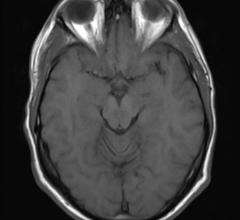

A new study based on magnetic resonance imaging (MRI) scans indicates that specific cardiovascular risk factors are associated with smaller regional brain volumes, which may be early indicators of Alzheimer’s disease and dementia. Those factors include alcohol consumption, smoking, obesity and diabetes. The study was published online in the journal Radiology.

Leading radiosurgery experts presented their experiences with Automatic Brain Metastases Planning software at the Novalis Circle Symposium during this year’s American Association of Physicists in Medicine (AAPM) annual meeting and exhibition. The software consistently and rapidly generates radiosurgery plans, allowing clinicians to efficiently treat up to 10 multiple brain metastases in one session while helping minimize radiation exposure to healthy surrounding tissue.

Researchers at the University of Kentucky’s Sanders-Brown Center on Aging are on the hunt for biomarkers that might serve as an early warning system for Alzheimer’s disease (AD).